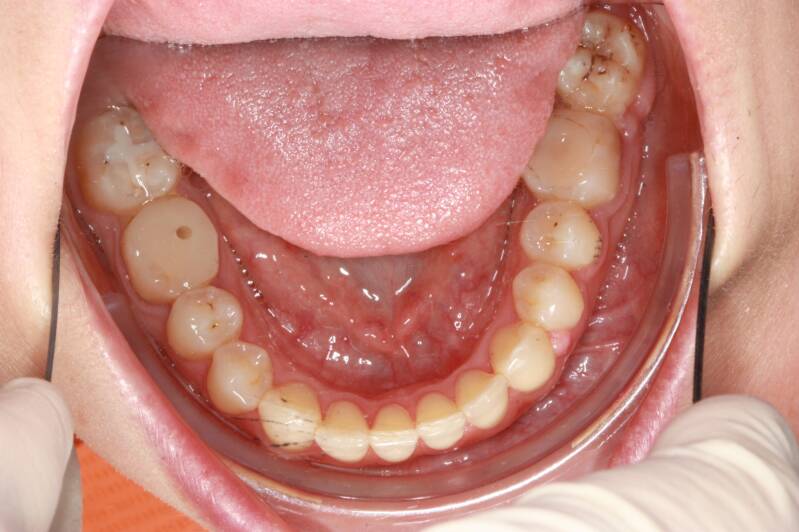

FOTO INIZIALI PRE TRATTAMENTO ORTODONTICO

PRIMA CLASSE CON AFFOLLAMENTO GRAVE SUPERIORE A SINISTRA CON PERDITA PRECOCE DEL SECONDO MOLARE INFERIORE SINISTRO

Abbiamo appena portato a termine questo caso che presentava in arcata superiore il primo premolare di sinistra completamente fuori arcata sovrapposto al secondo premolare ed il canino ruotato.

in arcata inferiore invece abbiamo estratto il secondo molare di sinistra perso per carie deostruente e mesializzato il terzo molare in modo da chiudere lo spazio e non ricorrere all'inserimento di protesi implantare.